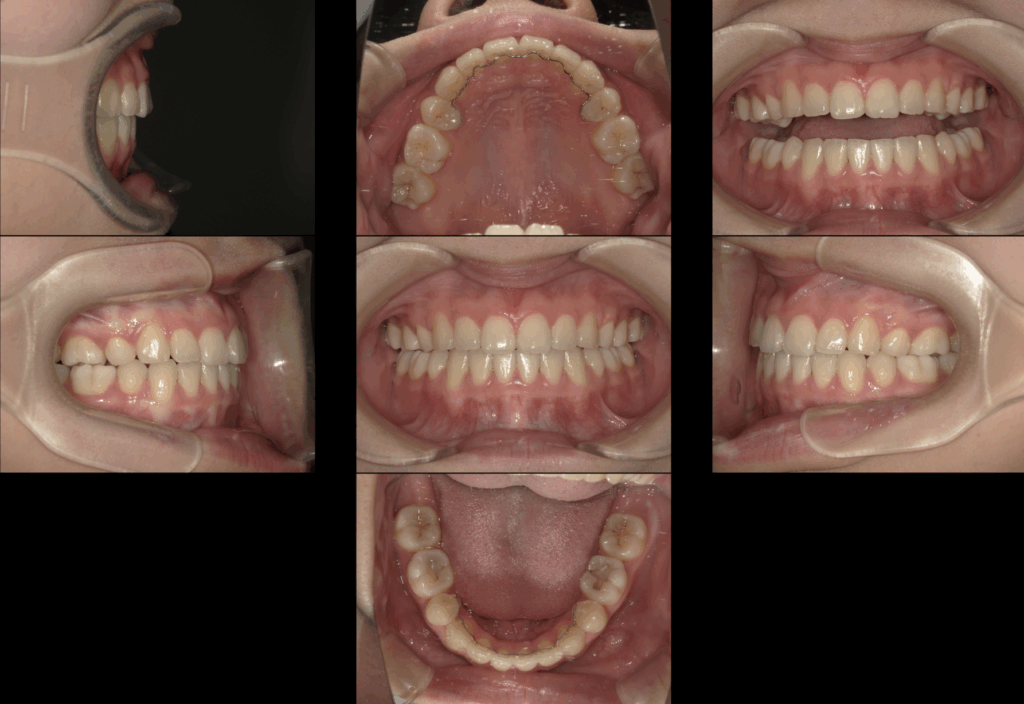

今回は、15歳の女性患者さんの矯正治療症例をご紹介します。

この症例は、単に歯並びを整えるだけでなく、顎関節の問題と咬合(かみ合わせ)を最優先に考えた治療が必要だったケースです。

抜歯を伴う矯正治療の選択

本症例では、歯列のスペース不足と口元のバランスを考慮し、上下左右の4番目の歯(第一小臼歯)を4本抜歯する治療計画としました。

2年半の矯正治療を経て

矯正装置を装着してから、治療期間は約2年半。

治療中も顎関節の状態を定期的にチェックしながら、慎重に歯の移動を進めました。

治療終了時には、

-

歯列はきれいに整い

犬歯誘導が回復

噛み合わせも安定

顎関節のクリック音もほぼ消失

という、機能面・審美面ともに非常に良好な結果を得ることができました。

治療後の今後の注意点|親知らずについて

治療後の状態は安定していますが、今後の注意点として**親知らず(第三大臼歯)**があります。